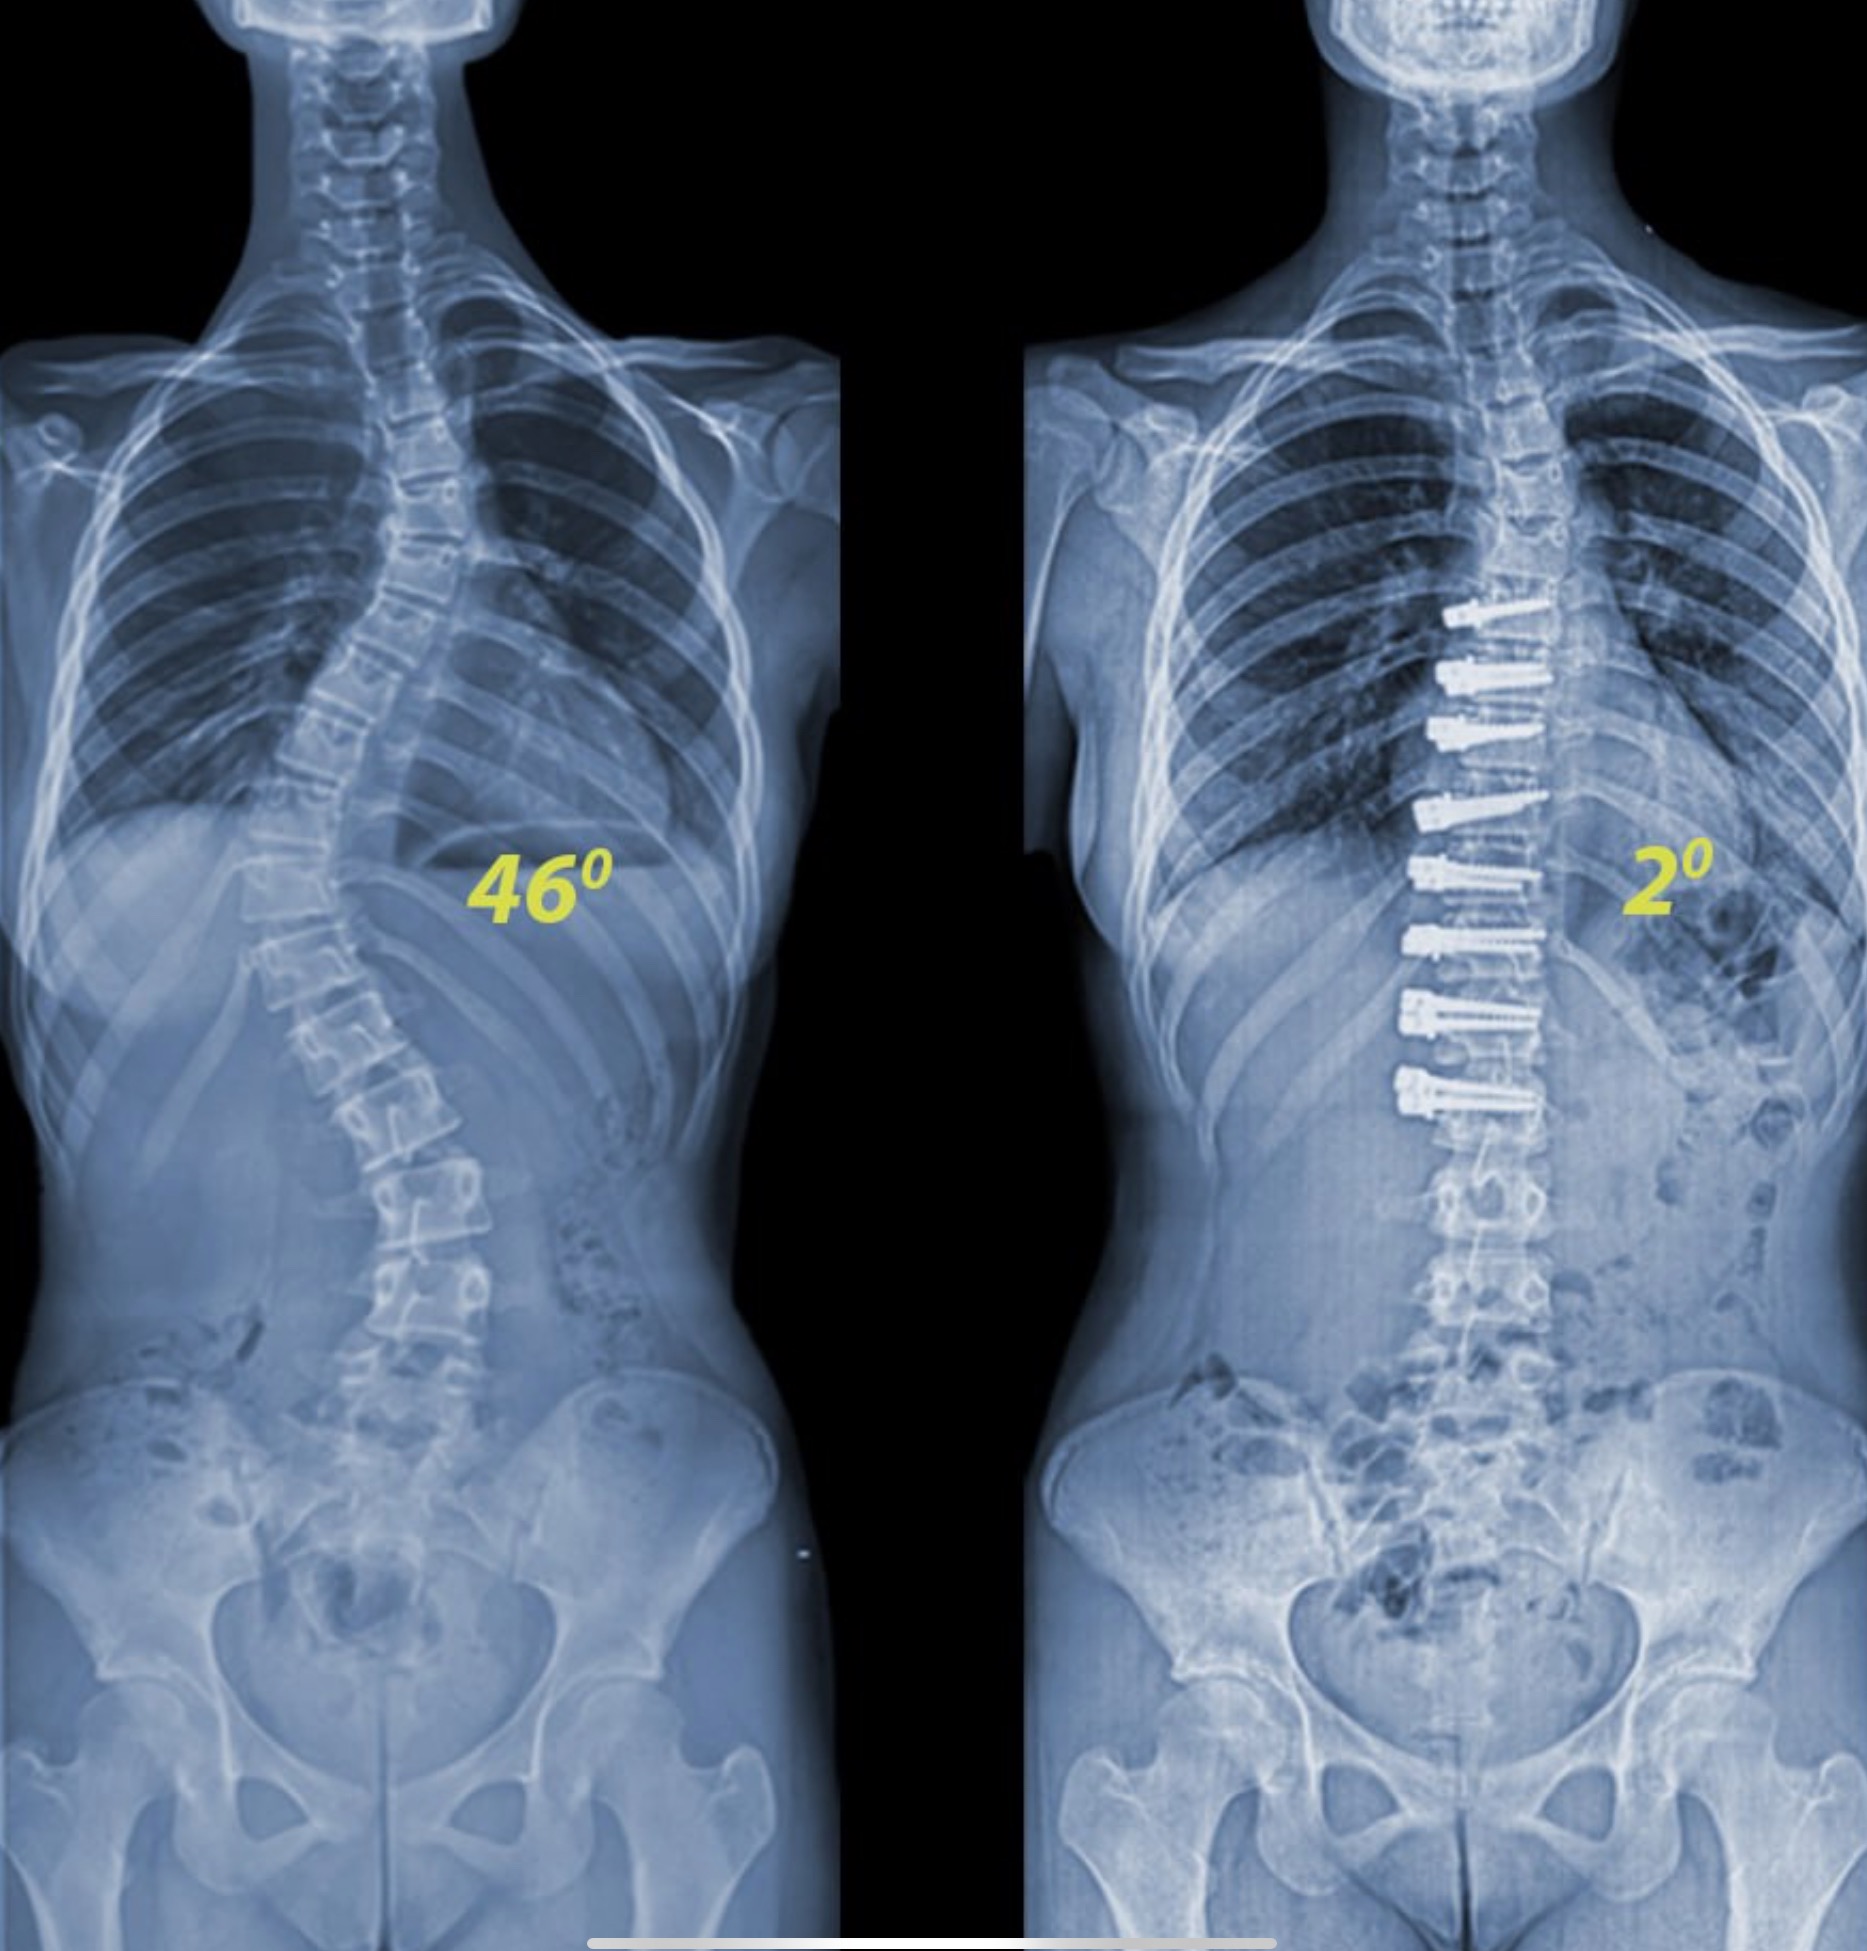

When I was 14 years old, I was diagnosed with idiopathic scoliosis. I wore braces and attempted managing it with many different techniques throughout my teens and 20s.

Today, my scoliosis is taking a toll on my ability to work, breath or sleep properly each day. And the pain has been exhausting.

Unfortunately, if left untreated this type of scoliosis can increase with age and affect spinal cord and nerves.

On a brighter note, I have been approved for Anterior Scoliosis Correction (ASC) which is a groundbreaking procedure. This new technology is quite remarkable as they use titanium instead of steel and they preserve mobility and muscles, while correcting the curvature like braces would a crooked smile.